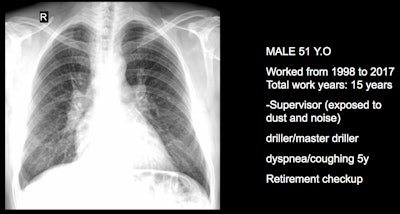

Three clinical cases courtesy of Dr. Luis Antonio Campos Calderon.

The International Labor Organization (ILO) International Classification of Radiographs of Pneumoconioses is used for epidemiological studies, screening, and surveillance of workers exposed to dust in the workplace, and clinical purposes, and the National Institute for Occupational Safety and Health (NIOSH) B Reader Program certifies physicians in the ILO classification system. Each case should discuss its ILO classification and brief comments about the workflow, he noted.

"Pneumoconiosis often develops slowly, and symptoms may not appear until significant damage has occurred. Early detection is crucial but can be difficult due to limited resources and awareness," Campos explained. "This diagnosis can be fraught because in Peru workers diagnosed with pneumoconiosis have rights to compensation and healthcare under current labor laws and social security systems. However, navigating the legal and bureaucratic processes to claim these benefits can be complex and challenging."

The main diagnostic criteria are: Work history (minimum 10 years exposure to silica dust or other particles); chest x-ray (micronodular pulmonary fibrosis, coded according to ILO classification); progression (image profusion increases over time, even after exposure cessation; irreversibility (disease is progressive and irreversible, no stable pneumoconiosis over time).